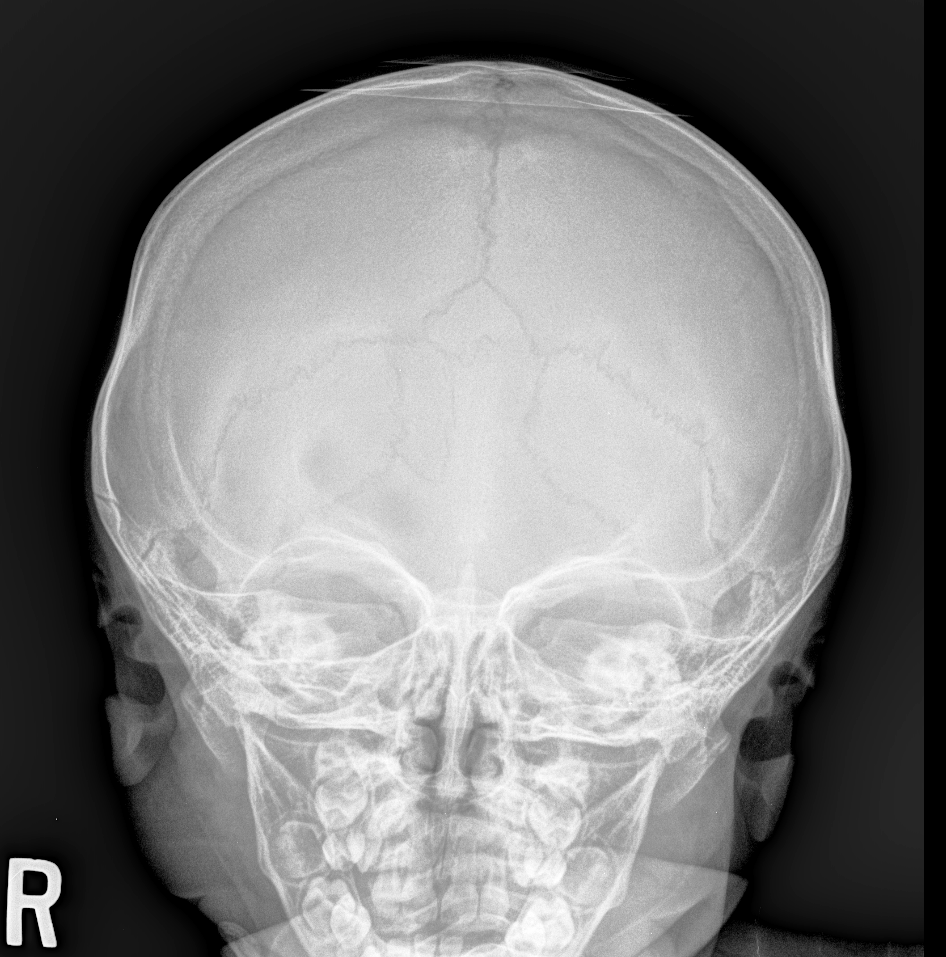

Info Images Findings Impression Reco/Acuity Case Images View Images / Launch Visage Case Notes History 2-month-old presents with decreased right arm movement, increased fussiness, and increased sleepiness for 2 days. Suspected non-accidental trauma. Exam Skeletal survey Prior Study none Dicom View Reference Material

Section 1 Submit Findings CB1550 Findings Skeletal Survey - Technique Check Skull AP/Lat Yes No Cervical and Thoracolumbar spine Yes No Chest X-Ray Yes No Ribs – Left/Right Oblique Yes No Abdominal X-Ray Yes No Pelvis with both hips Yes No Bilateral Humerus, Forearm, Hand Yes No Bilateral Femur, Tibia/fibula, feet Yes No Any additional lateral views of the extremities Yes No The exam is over or under penetrated. Yes No The exam may or may not be limited by overlying structures or soft tissues, body habitus, patient positioning, support devices, or motion. Yes No The area of concern is indicated by the patient, technologist, or care provider. Yes No The area of concern is included on the exam. Yes No Soft Tissues There is soft tissue swelling, indistinctness of fat/muscle planes, gas, or laceration in the area of clinical concern. Yes No There is an effusion, fat pad displacement, or fat fluid level. Yes No There is a radiodense or lucent foreign body. Yes No There are other densities, calcifications, post-surgical changes, or support devices in the soft tissues. Yes No Any support lines/tubes. Yes No Bone There is a break or interruption of the continuity of the cortical or cancellous bone. Yes No There is overriding of the trabeculae with apparent sclerosis. Yes No There is displacement of a fracture fragment. Yes No There is bowing of the bone in addition to the fracture at the apex of the bowed bone concerning for the greenstick. Yes No There is a spiral fracture of the leg concerning for toddler’s fracture. Yes No There is abnormal angulation or bulging of the cortical surface relative to the normal cortex which could be from a buckle or torus fracture. Yes No There is a displaced fragment which may be from avulsion by a tendon, ligament, or joint capsule or from a comminuted or other fracture. Yes No The stress trabeculae or other trabeculae of the cancellous bone are interrupted or otherwise abnormal. Yes No There is subperiosteal or endosteal reaction which could indicate a healing or subacute fracture or other abnormality. Yes No There is hard/soft callus formation. Yes No There is remodeling of the bone. Yes No There is a corner fracture or metaphyseal lesion that could be from nonaccidental trauma. Yes No There are multiple fractures of different ages. Yes No There are vertebral body/spinous process fractures. Yes No There are rib fractures. Location - posterior or lateral. Yes No There is scapular/sternal fracture. Yes No There are fractures of the digits. Yes No There are wormian bones. Yes No There are intrasutural bones. Yes No There is metaphyseal abnormality (lucencies, increased density, erosion) which may be from something other than injury such as stress, metabolic disease (e.g. rickets with loss or distortion of the zone of the provisional calcification), neoplasm (e.g. leukemia), heavy metals, inflammation, or infection. Yes No There are metaphyseal spurs. Yes No There are bony deformities involving multiple bones. Yes No The bones are gracile. Yes No There are non-healing fractures. Yes No There is/are focal or multifocal lytic/lucent, blastic/sclerotic or mixed density lesion(s) or other abnormality. Yes No Overall bone density is increased or decreased with or without thinning or thickening of the cortical or cancellous bone. Yes No Growth plates, ossification centers, apophyses The growth plate(s) is/are abnormal. Yes No There is widening of the physis from a fracture with or without displacement of the epiphysis (Salter-Harris I). Yes No There is a fracture through the physis which then extends into the metaphysis with or without angulation or displacement (S-H II). Yes No There is a fracture through the physis which then extends into the epiphysis and is intra-articular, with or without angulation or displacement (S-H III). Yes No There is a fracture through the metaphysis, physis, and epiphysis which extends into the joint space with or without angulation or displacement (S-H IV). Yes No There is narrowing of the physis from a compression fracture (S-H V). Yes No The apophysis, epicondyle, secondary ossification center, or accessory ossicle is displaced or otherwise abnormal. Yes No The ossification centers are underdeveloped. Yes No Joints and alignment There is an effusion, fat pad displacement, or fat fluid level. Yes No The epiphysis or subchondral bone is fractured, interrupted, flattened, compressed, impacted, displaced, or otherwise abnormal. Yes No There is an intra-articular loose body or chondrocalcinosis. Yes No The joint is widened, narrowed, dislocated, malaligned, or incongruent. Yes No There is pseudoarthrosis. Yes No Other findings There are developmental changes or other anatomic variants or other existing conditions that may or may not be contributing to symptoms which can or should be further evaluated non-emergently or are otherwise incidental. Yes No The remainder of the exam is abnormal for age. Yes No The lungs show focal airspace opacity. Yes No There is pneumothorax. Yes No There is organomegaly. Yes No There is intra-abdominal calcification. Yes No There is displacement of the bowel loops. Yes No There is free intraperitoneal air. Yes No The bowel loops are dilated/obstructed. Yes No There is paraspinal soft tissue abnormality. Yes No